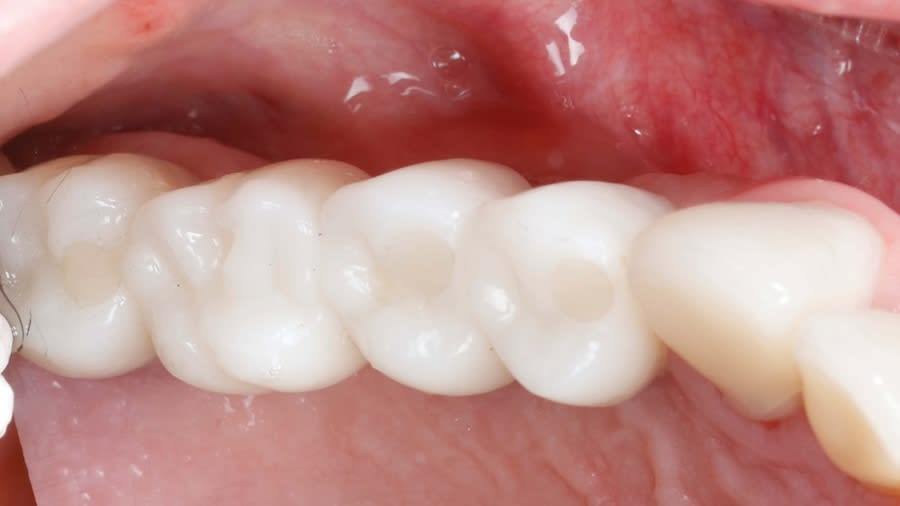

Case 1 (Figure 3 through Figure 24) depicts a 3-year follow-up of combined osseodensification sinus protocol IV in a severely resorbed maxillary ridge with ≤0.5 mm bone height in molar sites and horizontal deficiency at the first premolar site, using a two-stage approach for implant placement.

Case 2 (Figure 25 through Figure 36) illustrates a 3-year follow-up of the osseodensification sinus protocol IV in a severely resorbed right maxillary ridge with <0.5 mm bone height in molar sites, using a two-stage approach for implant placement.

Case 3 (Figure 37 through 44) shows a case of significant trauma history with a 3-year follow-up of the osseodensification sinus protocol IV in a severely resorbed right maxillary ridge with ≤0.5 mm bone height in molar sites, using a two-stage approach for implant placement.